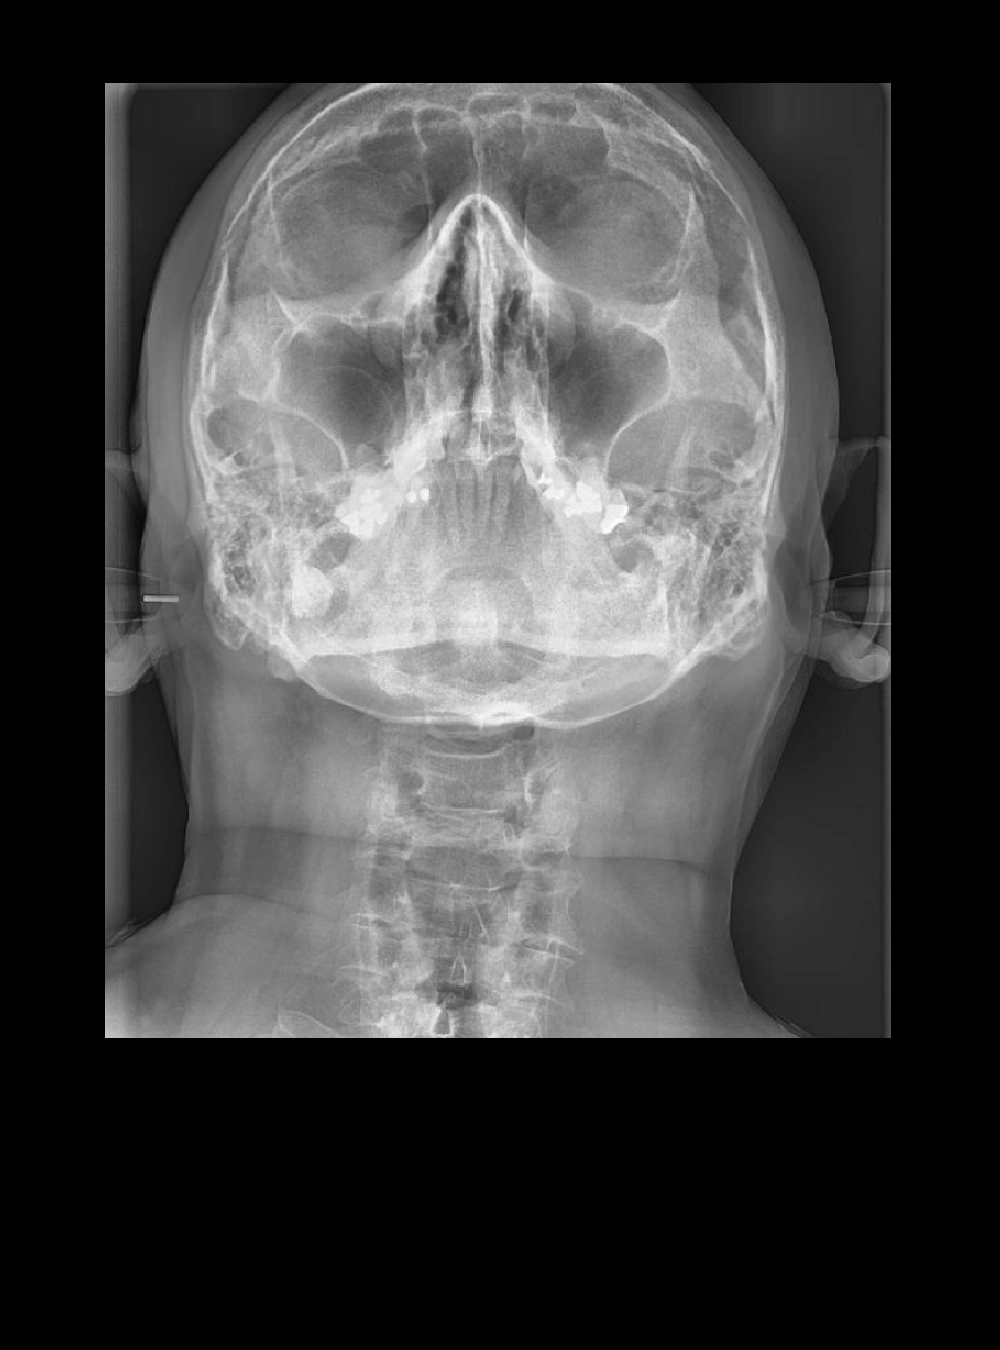

Rx P-A de Cráneo

Rx A-P de Cráneo

• A-P de Cráneo Antero Posterior

• P-A de Cráneo Postero Anterior